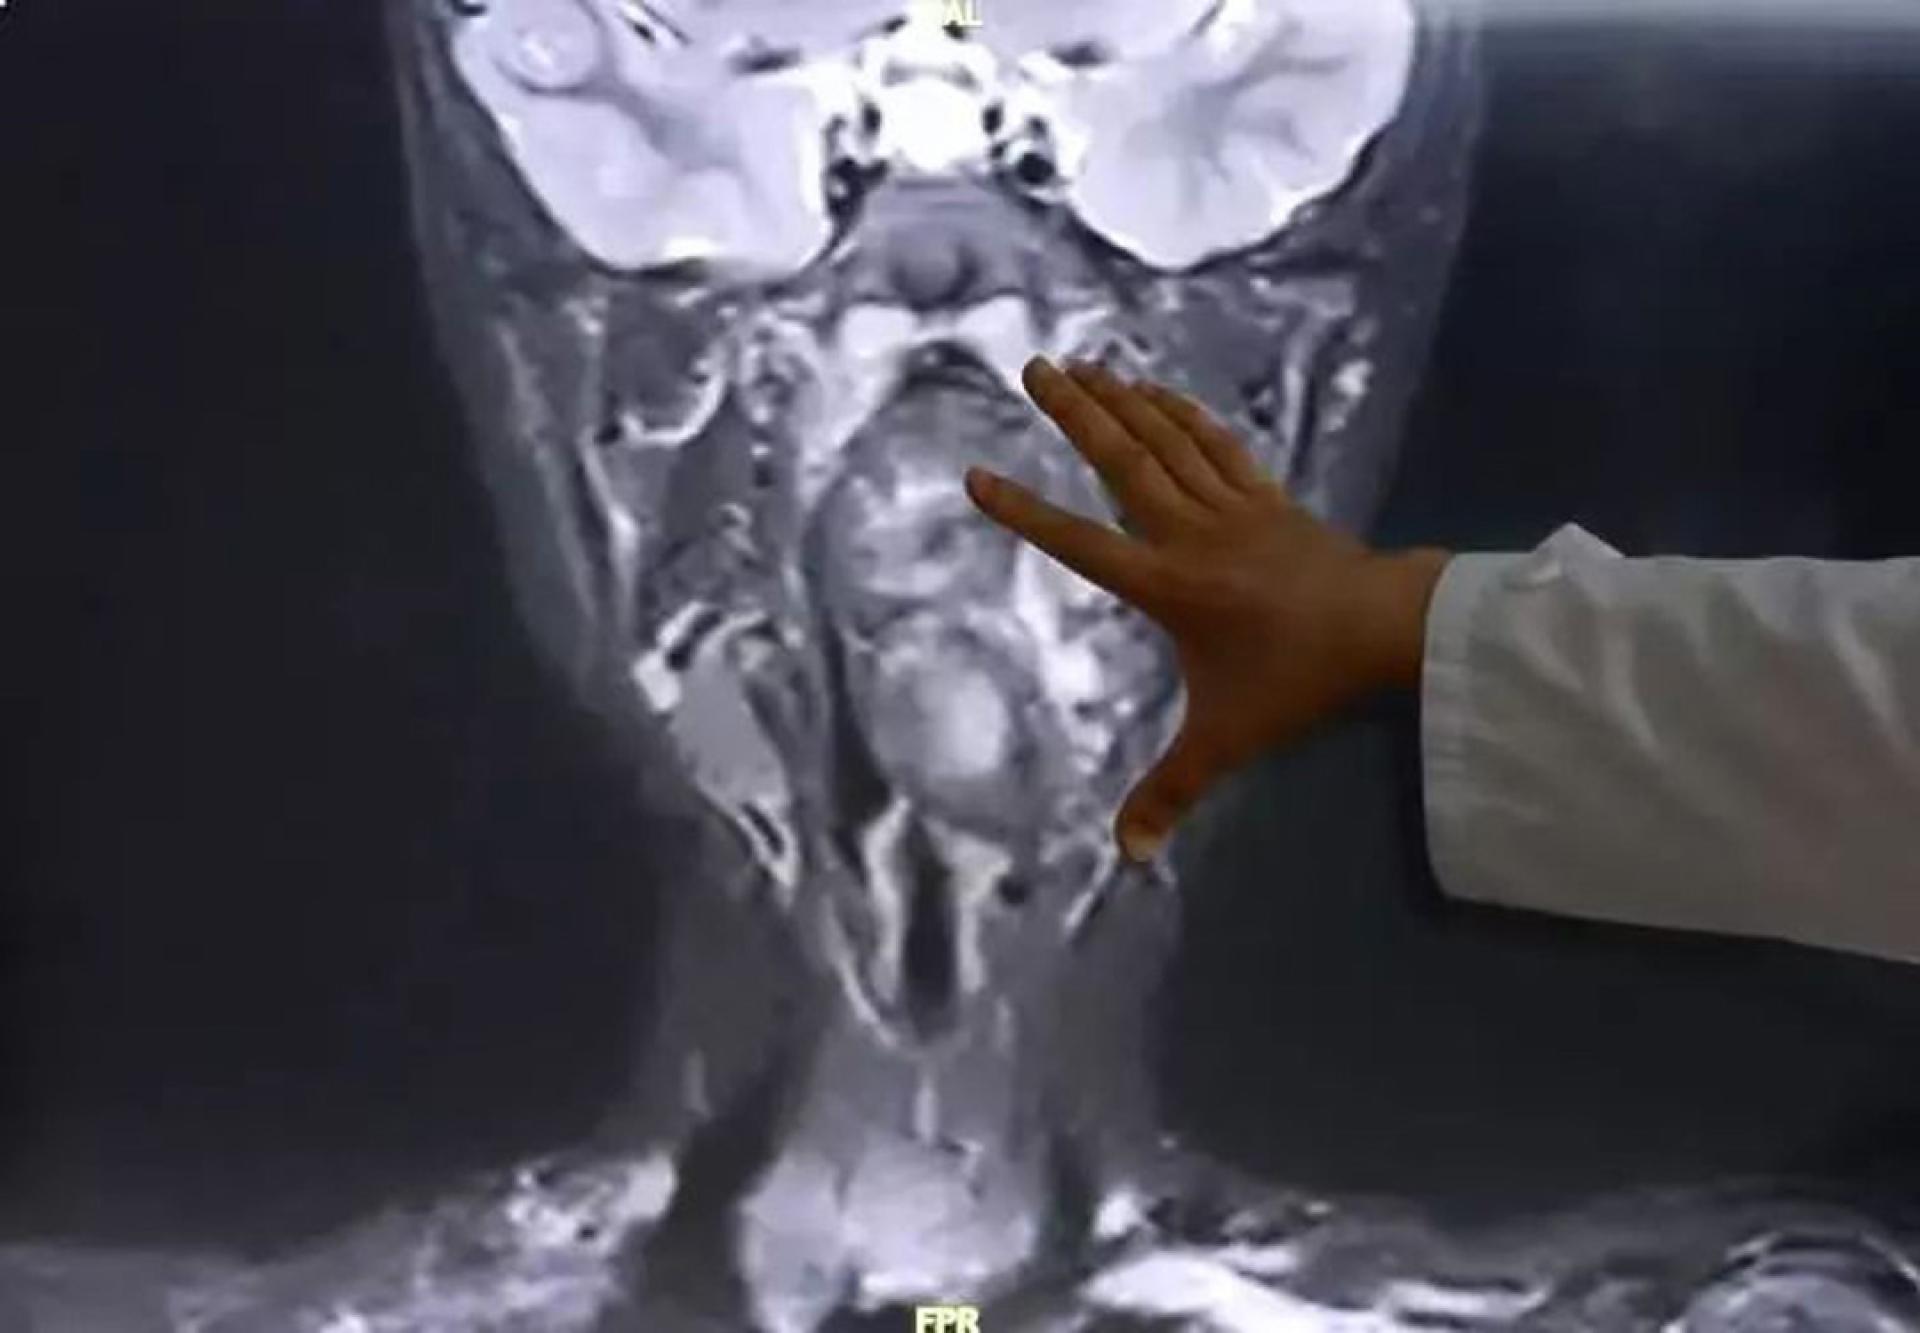

医生检查后发现情况极为凶险,小亮的口咽腔仅约8厘米,但该枚大小达6.6厘米的肿瘤已占据大部分气道,仅留下一条狭窄缝隙用作呼吸,若不尽快处理,随时有窒息死亡的危险。

为小亮诊治的耳鼻咽喉头颈外科副主任陈超医生解释,该枚肿瘤是由生殖细胞演变而成的“畸胎瘤”。他指出:“我们可以从中看到有脂肪、有软骨。这本应是一对双胞胎,一个正常发育成现在这个人,另一个则可能残留在此处,发育成了畸胎瘤。”

医生表示,畸胎瘤多为良性,但一般常见于腹腔,生长在儿童咽喉部且体积如此巨大的病例则极为罕见。更棘手的是,肿瘤紧贴颈部大动脉,令手术风险极高。